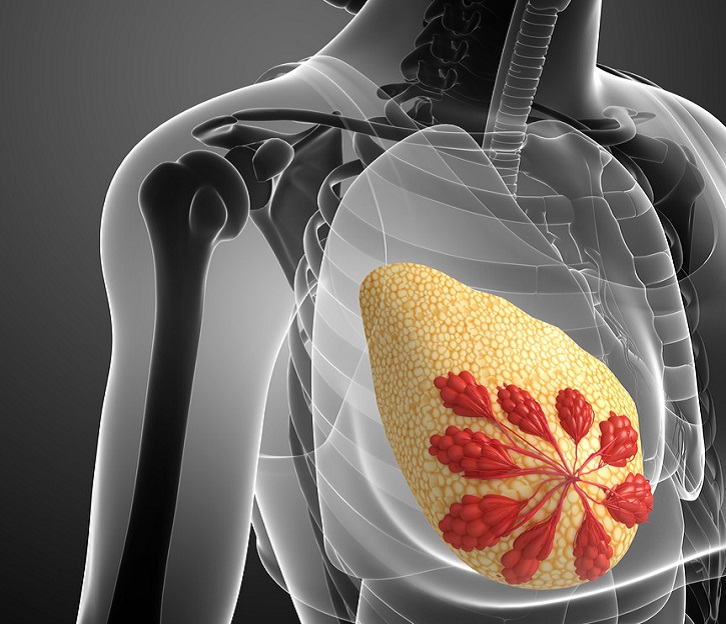

乳房里的淋巴结是什么样的呢?-